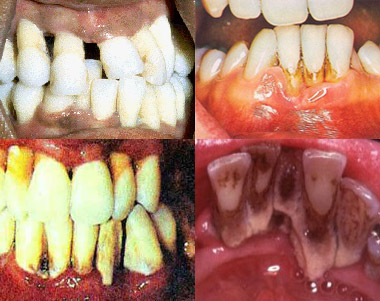

Những dấu hiệu cần lưu ý:

- Chảy máu nướu khi chải răng; Nướu đỏ, sưng, tách ra khỏi răng; Hơi thở hôi dai dẳng; Có ổ mủ hoặc có mủ chảy ra ở giữa răng và nướu ở vùng cổ răng; Răng lung lay hoặc thưa ra, đặc biệt khi nhai. Khi gặp những dấu hiệu trên nên đến gặp nha sĩ. Tuy nhiên, thông thường bệnh nha chu xảy ra không rõ ràng, bởi phần lớn thời gian diễn tiến bệnh không kèm theo triệu chứng đau đặc hiệu, vì vậy việc khám răng miệng định kỳ, trong đó khám toàn diện mô nha chu, là rất cần thiết.